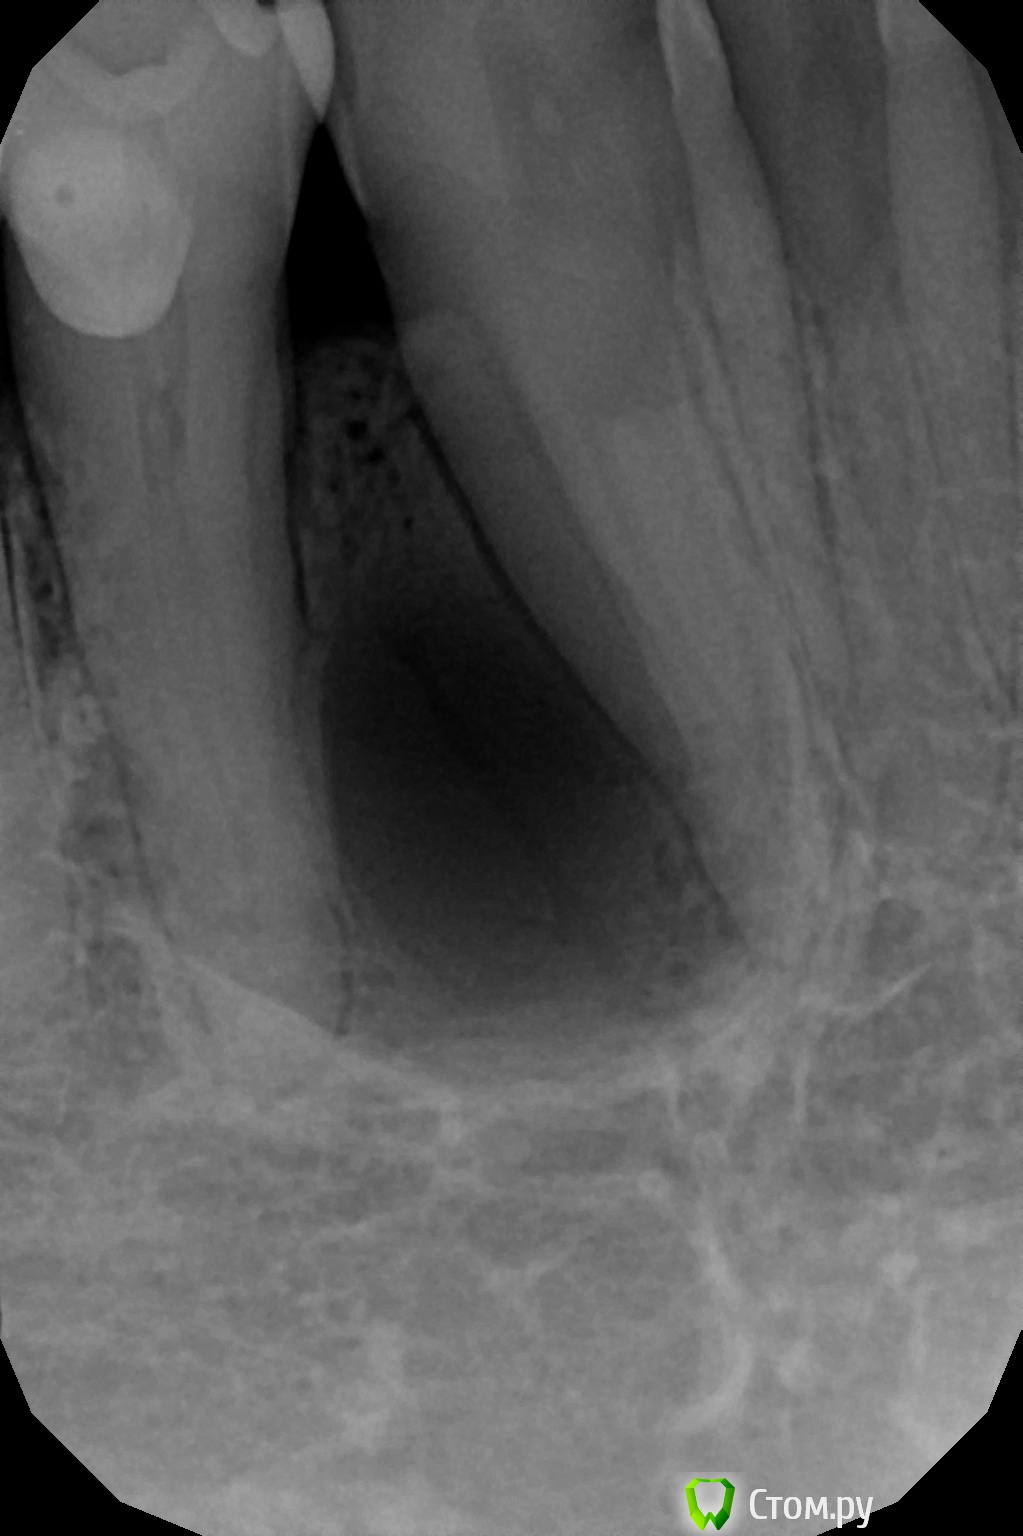

faity Опубликовано 27 мая, 2014 Поделиться Опубликовано 27 мая, 2014 вчера пришел пациент на удаление и имплантацию, а у него такое говорит уже лет 5, то "надувается", то "сдувается". причем в размерах уменьшается при определенных обстоятельствах, со слов пациента: "она когда выростает сильно(ком.авт: на снимке это не сильно, по его параметрам большой размер- когда зубы перестают смыкаться), я литр водки выпиваю- и она сдувается, раз в полгода так примерно и пью" на рентгене вот так думаю биопсию сделать, если не онкогенеза- иссеку и аугментирую, думаю 4.3 и 4.4 не трогать.какие мысли, предложения? 1 1 Ссылка на комментарий

Alexey Doc Опубликовано 27 мая, 2014 Поделиться Опубликовано 27 мая, 2014 Возможно даже парадентальная Ссылка на комментарий

red_butler Опубликовано 27 мая, 2014 Поделиться Опубликовано 27 мая, 2014 Боковая пародонтальная киста Ссылка на комментарий

DokDent Опубликовано 27 мая, 2014 Поделиться Опубликовано 27 мая, 2014 А что это в "кисте"? Очень похоже на сосуд 2 Ссылка на комментарий

faity Опубликовано 27 мая, 2014 Автор Поделиться Опубликовано 27 мая, 2014 1. Не важно, любое ксено, возможно и без графта обойтись2. Любая коллагеновая3. Лоскутом4. Проба на витальность до вмешательства - эод и термометрия хладагентом, у меня эндофроста нет, хотя бы ледышку приложить1 я думаю из области вмешательства скребком набрать2 у нас только биогайд закупают, так можно чем угодно, согласен3 язычно пришью, а вестибулярно простолоскутом натянуть? не слетит?4 согласен может на "ты"? давно вроде общаемся, меня Андрей зовут А что это в "кисте"? Очень похоже на сосуд может сосуд, а может линия перелома, вскрытие покажет Ссылка на комментарий